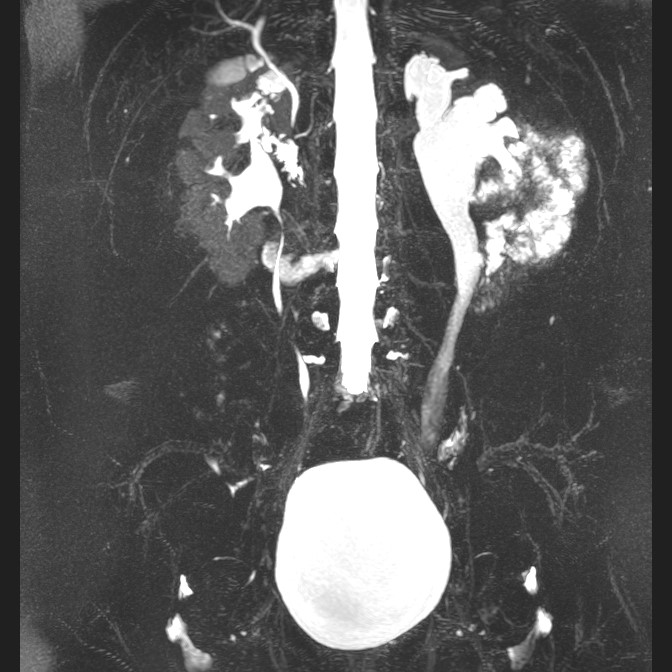

L'Uro Risonanza Magnetica aiuta i bambini con problemi urinari

L’Irccs Burlo Garofolo è all’avanguardia nello studio di bambini con dilatazioni delle vie urinarie grazie all’impiego dell’innovativa tecnica dell’Uro Risonanza Magnetica. Il dottor Claudio Granata, Direttore della Struttura Complessa di Radiologia Pediatrica del Burlo, ci spiega cos’è e quali sono i suoi vantaggi.

Si tratta di una tecnica impiegata per studiare bambini con dilatazioni delle vie urinarie, da un punto di vista sia morfologico, sia funzionale. Queste dilatazioni possono, alla lunga, portare a danni renali. Grazie all’Urorisonanza è possibile capire se sia presente qualche ostacolo meccanico, legato a una malformazione, che impedisce il normale deflusso dell'urina dal rene lungo le vie urinarie. Questa metodica fornisce tutti gli elementi necessari utili a capire se sia il caso o meno di intervenire chirurgicamente.

Tipicamente ci vengono mandati bambini dai nefrologi che li seguono nel tempo. Infatti, come già accennato, alcuni presentano queste problematiche fin dalla gravidanza. Non tutte le dilatazioni sono legate alla presenza di ostacoli meccanici e talvolta possono semplicemente essere monitorate nel tempo, senza necessità di intervento. Altri invece, in cui le dilatazioni sono causate da malformazioni che creano un vero e proprio ostacolo meccanico, possono sviluppare importanti problemi renali che meritano un approfondimento. Grazie all’Uro Risonanza è possibile stabilire se ci sia o meno un impedimento al deflusso dell’urina.

Sicuramente l’Uro Risonanza fornisce un dettaglio anatomico e funzionale finissimo, molto superiore rispetto ad altre metodiche precedentemente utilizzate come l’ecografia o esami scintigrafici che utilizzano radiofarmaci, somministrati per via endovenosa, che si localizzano nei reni, visualizzabili grazie alla componente radioattiva. L’enorme precisione dell’Uro Risonanza è fondamentale per consentire al chirurgo e al terapeuta di prendere accurate decisioni, capendo se ci sia indicazione o meno a intervenire chirurgicamente. In caso affermativo il chirurgo potrà fare un bilancio pre-operatorio di alta qualità.

Inoltre, essendo una tecnica che non sfrutta radiazioni ionizzanti, consente di eseguire lunghi follow-up nel tempo, privi di qualunque rischio.